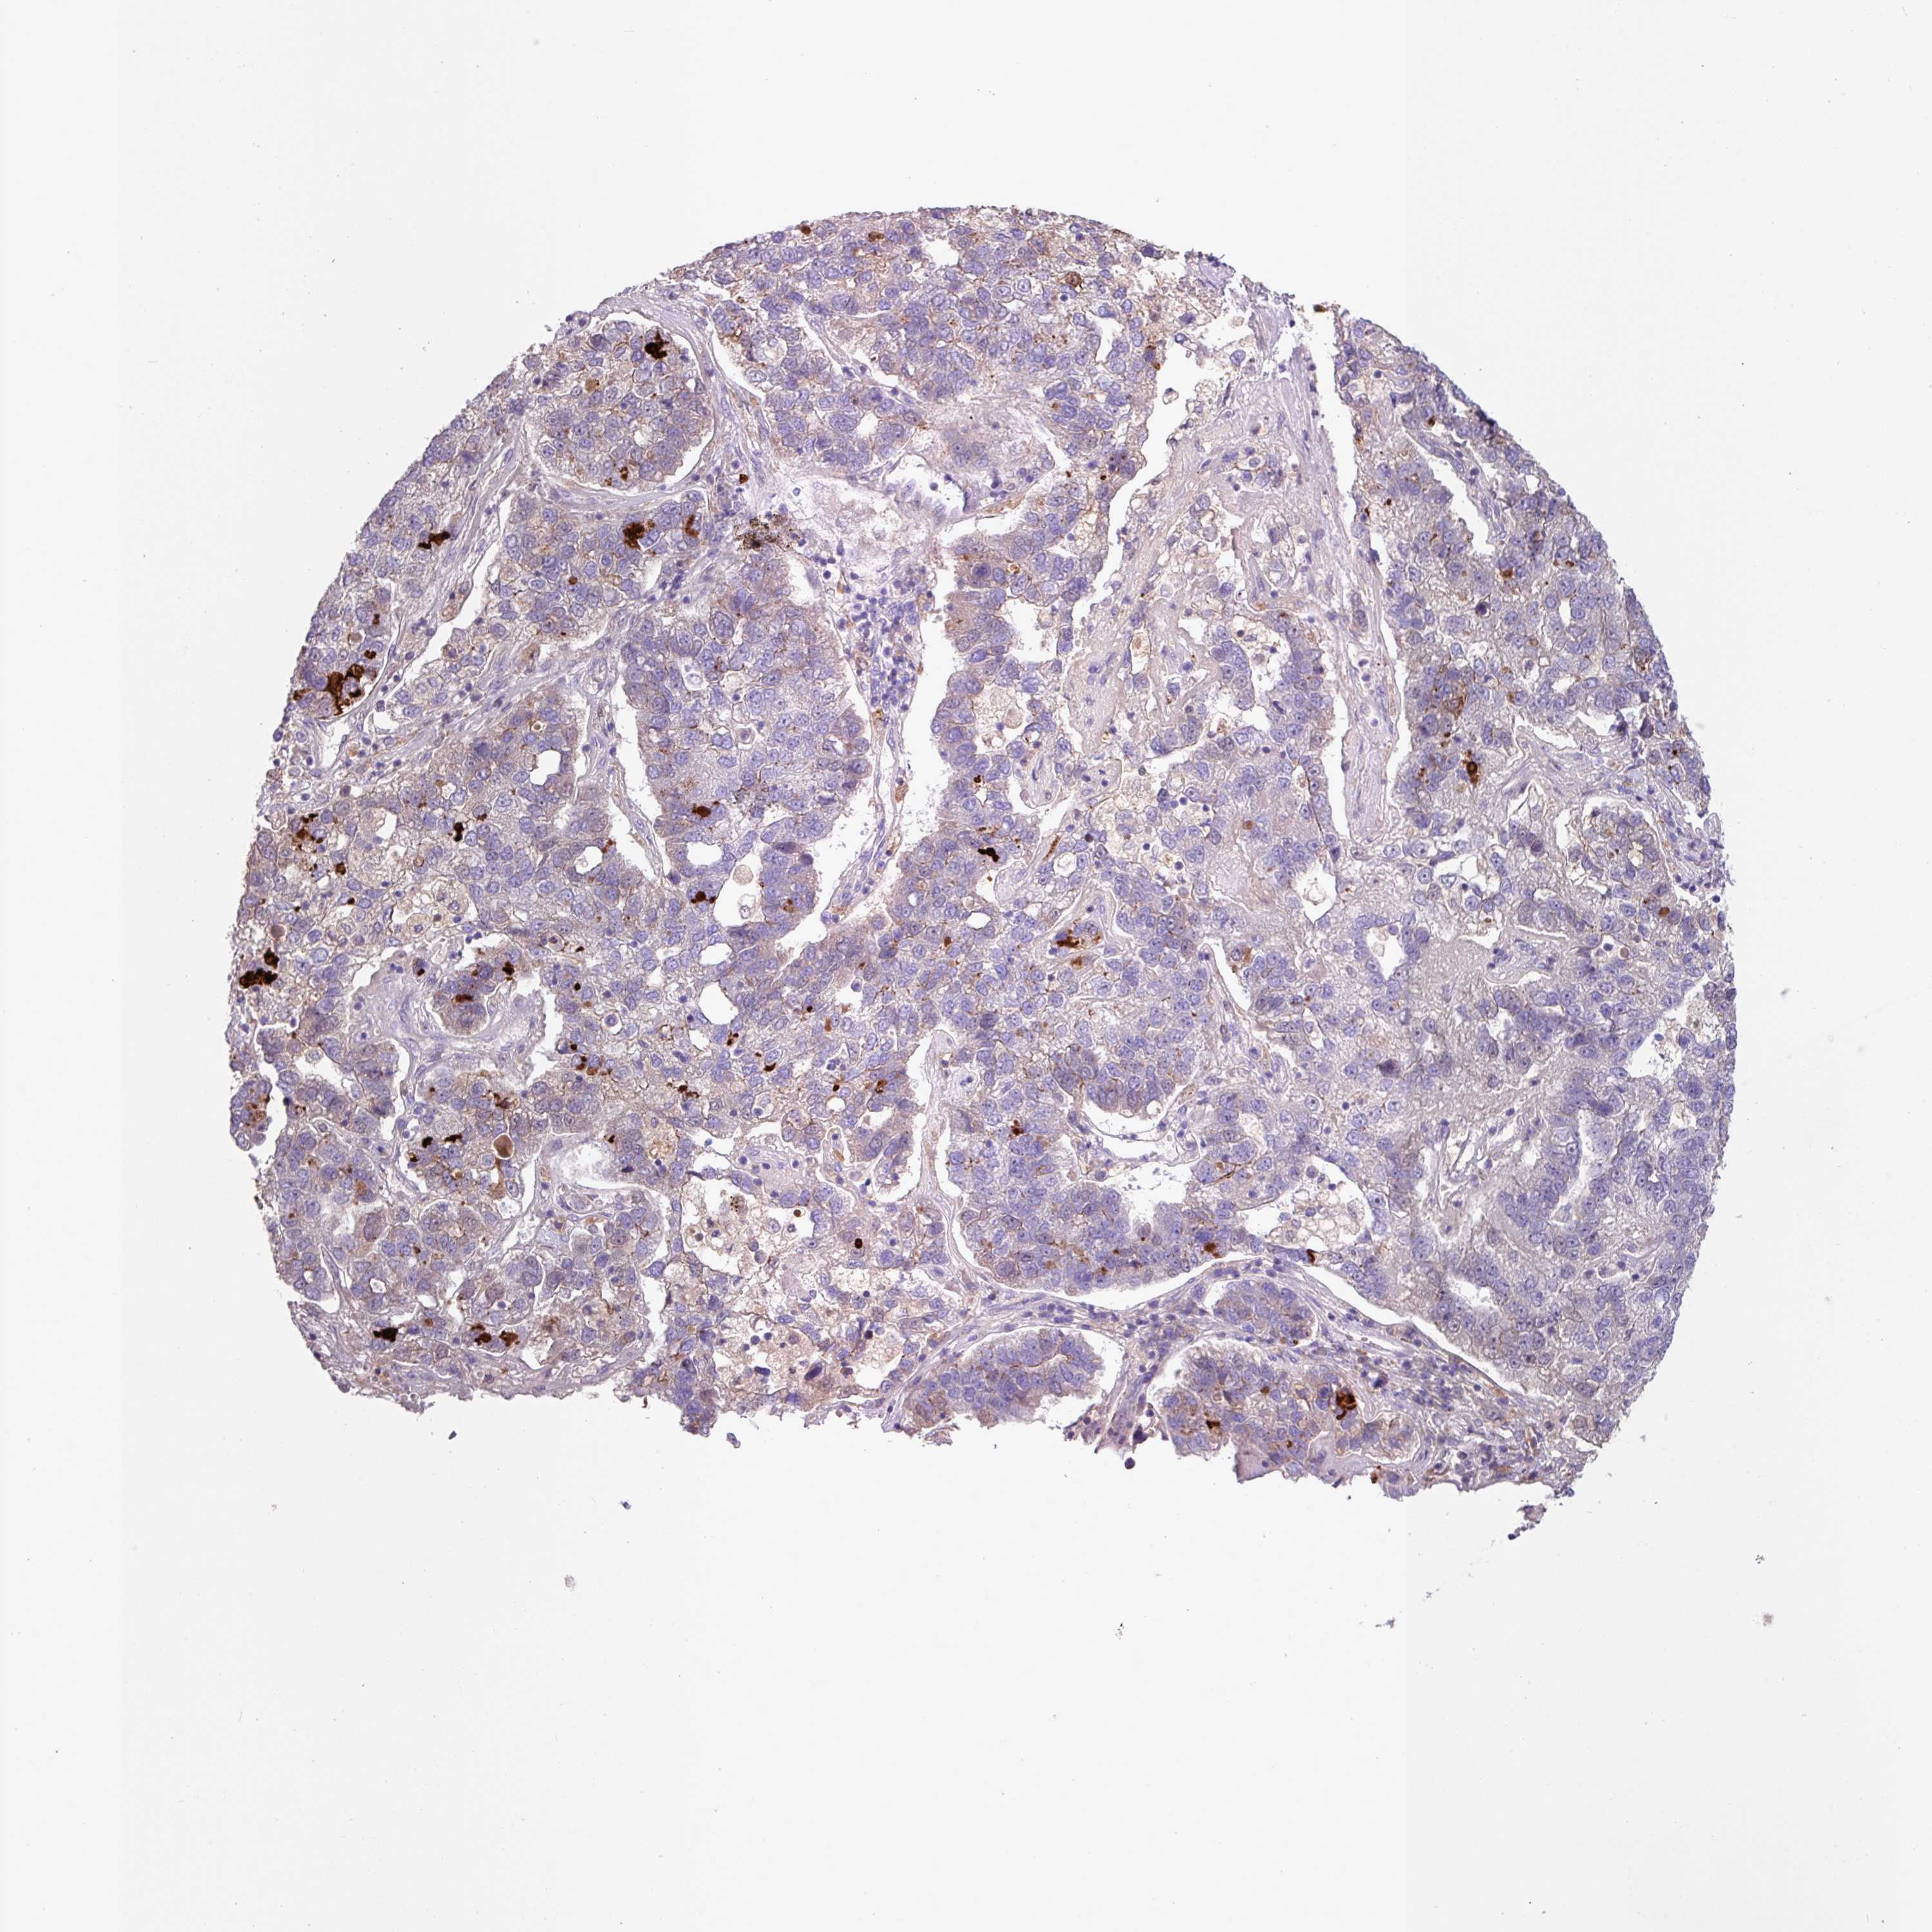

PANCREATIC CANCER - Protein expressioni

A mouse-over function shows sample information and annotation data. Click on an image to view it in a full screen mode. Samples can be filtered based on level of antibody staining by selecting one or several of the following categories: high, medium, low and not detected. The assay and annotation is described here.

Note that samples used for immunohistochemistry by the Human Protein Atlas do not correspond to samples in the TCGA dataset.

Antibody stainingi

Antibody staining in the annotated cell types in the current human tissue is reported as not detected, low, medium, or high, based on conventional immunohistochemistry profiling in selected tissues. This score is based on the combination of the staining intensity and fraction of stained cells.

Each image is clickable and will lead to virtual microscopy that enables deeper exploration of all samples and also displays staining intensity scores, fraction scores and subcellular localization as well as patient and tissue information for each sample.

Antibody HPA052835

Staining

High

Medium

Low

Not detected

Intensity

Strong

Moderate

Weak

Negative

Quantity

>75%

75%-25%

<25%

None

Location

Nuclear

Cytoplasmic/membranous

Cytoplasmic/membranous,nuclear

Adenocarcinoma, NOS